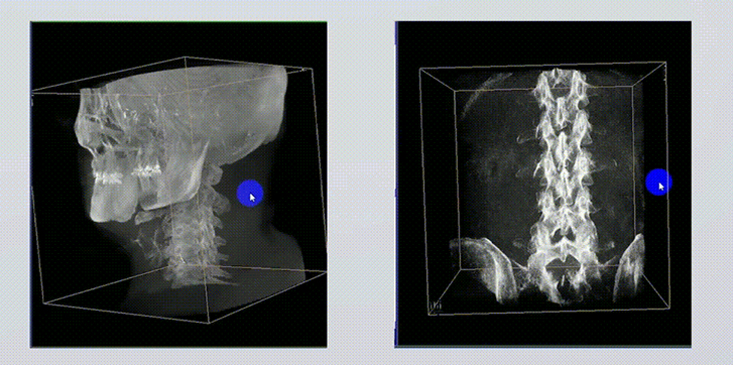

1、術(shù)中實時三維成像

術(shù)中三維成像和橫斷面圖像提供多角度的手術(shù)診斷信息,輔助醫(yī)生進(jìn)行術(shù)中評估判斷,諸如骨折復(fù)位情況和內(nèi)植入螺釘?shù)某叽绾臀恢?,輔助手術(shù)更好地完成。

2、三維成像視野大

提供更大的術(shù)中三維成像視野,采集更多圖像信息,可一次拍全全段頸椎、全段腰椎、七節(jié)胸椎、雙側(cè)骶髂關(guān)節(jié)、股骨頭及單側(cè)盆骨。